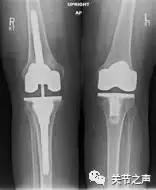

全膝关节表面置换术:适用于重度的关节磨损、严重的关节畸形的病人,全膝关节表面置换术到目前来讲是比较成熟的手术技术,而且也只是关节表面的置换,所以不必过分畏惧手术,但膝关节置换手术对手术技术和经验要求极高,尽可能找关节专业的医生做这样的手术。